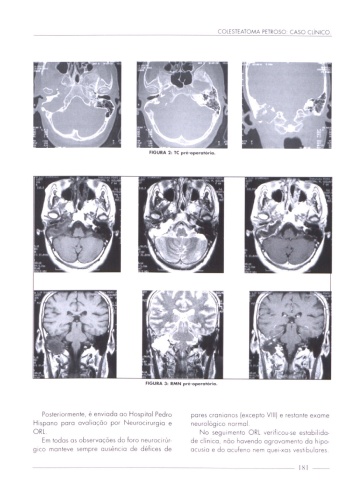

FIGURA 3: RMN pré-oporo'ório.

Posrenormenre, é envnodo 00 Hospital Pedro pores cromonos (excepto VIII) e restante exame

Hispano poro ovoluoçóo por Neurocirurgia e neurológico normal

ORI. No segunmemo ORL ver|f|c0use CSYGbIIIdC'

Em todos as observações do foro neurocirúr de climco não havendo agravamento do hlpO'

gICO manteve sempre ouséncno de défices de OCUSIO e do ccufeno nem Queues vesr'bulores